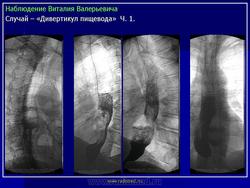

Клиническая картина, предварительный диагноз У большинства больных, особенно с небольшими дивертикулами, стойкие симптомы заболевания могут отсутствовать. Лишь эпизодически возникает дисфагия, чаще при поспешной еде, еде всухомятку. При дивертикулах больших размеров дисфагия возникает почти при каждом приеме пищи, в положении лежа может наблюдаться регургитация (обратное затекание) содержимого дивертикула в пищевод и глотку, срыгивание. Эти больные могут отмечать неприятный запах (вследствие разложения задержавшихся в пищеводе пищевых остатков). Основное значение для диагностики дивертикула имеет контрастное рентгенологическое исследование, при котором устанавливают дивертикул, определяют его размеры, форму, наличие или отсутствие в нем контрастной массы и пищевых остатков. Небольшие дивертикулы средней и нижней трети пищевода, в которых не задерживается контрастная масса, лучше выявляются при рентгенологическом исследовании пищевода в положении больного лежа. Небольшие бессимптомно протекающие дивертикулы часто являются случайной рентгенологической находкой при контрастном рентгенологическом исследовании, проводимом по другому поводу. Дивертикулы, соединяющиеся с пищеводом широким сообщением, выявляют при эзофагоскопии. Со временем дивертикулы нередко увеличиваются в размерах. При плохом опорожнении дивертикула (при мешкообразной форме, с дном, расположенным значительно ниже шейки дивертикула) в нем задерживается пища (особенно плохо разжеванные куски), которая может разлагаться; велика опасность возникновения дивертикулита, а затем - медиастинита. В дивертикулите могут задерживаться и проглоченные инородные тела (кусочки куриной или рыбьей кости и др.).

У большинства больных, особенно с небольшими дивертикулами, стойкие симптомы заболевания могут отсутствовать. Лишь эпизодически возникает дисфагия, чаще при поспешной еде, еде всухомятку. При дивертикулах больших размеров дисфагия возникает почти при каждом приеме пищи, в положении лежа может наблюдаться регургитация (обратное затекание) содержимого дивертикула в пищевод и глотку, срыгивание. Эти больные могут отмечать неприятный запах (вследствие разложения задержавшихся в пищеводе пищевых остатков). Основное значение для диагностики дивертикула имеет контрастное рентгенологическое исследование, при котором устанавливают дивертикул, определяют его размеры, форму, наличие или отсутствие в нем контрастной массы и пищевых остатков. Небольшие дивертикулы средней и нижней трети пищевода, в которых не задерживается контрастная масса, лучше выявляются при рентгенологическом исследовании пищевода в положении больного лежа. Небольшие бессимптомно протекающие дивертикулы часто являются случайной рентгенологической находкой при контрастном рентгенологическом исследовании, проводимом по другому поводу. Дивертикулы, соединяющиеся с пищеводом широким сообщением, выявляют при эзофагоскопии. Со временем дивертикулы нередко увеличиваются в размерах. При плохом опорожнении дивертикула (при мешкообразной форме, с дном, расположенным значительно ниже шейки дивертикула) в нем задерживается пища (особенно плохо разжеванные куски), которая может разлагаться; велика опасность возникновения дивертикулита, а затем - медиастинита. В дивертикулите могут задерживаться и проглоченные инородные тела (кусочки куриной или рыбьей кости и др.).